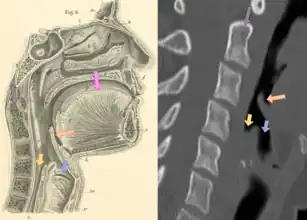

CT imaging showing the "halloween sign"

Left column: Normal epiglottis. Right column: Epiglottitis.

On lateral C-spine X-ray, the thumbprint sign describes a swollen, enlarged epiglottis.[10] A normal X-ray, however, does not exclude the diagnosis.[10] An ultrasound may be helpful if specific changes are present, but its use (as of 2018) is in the early stages of study.[10]

On CT imaging, the "Halloween sign" describes an epiglottis of normal thickness. It can safely exclude the acute epiglottitis. Furthermore, CT imaging can help to diagnose other conditions such as peritonsillar abscess or retropharyngeal abscess which have similar clinical features.[21]